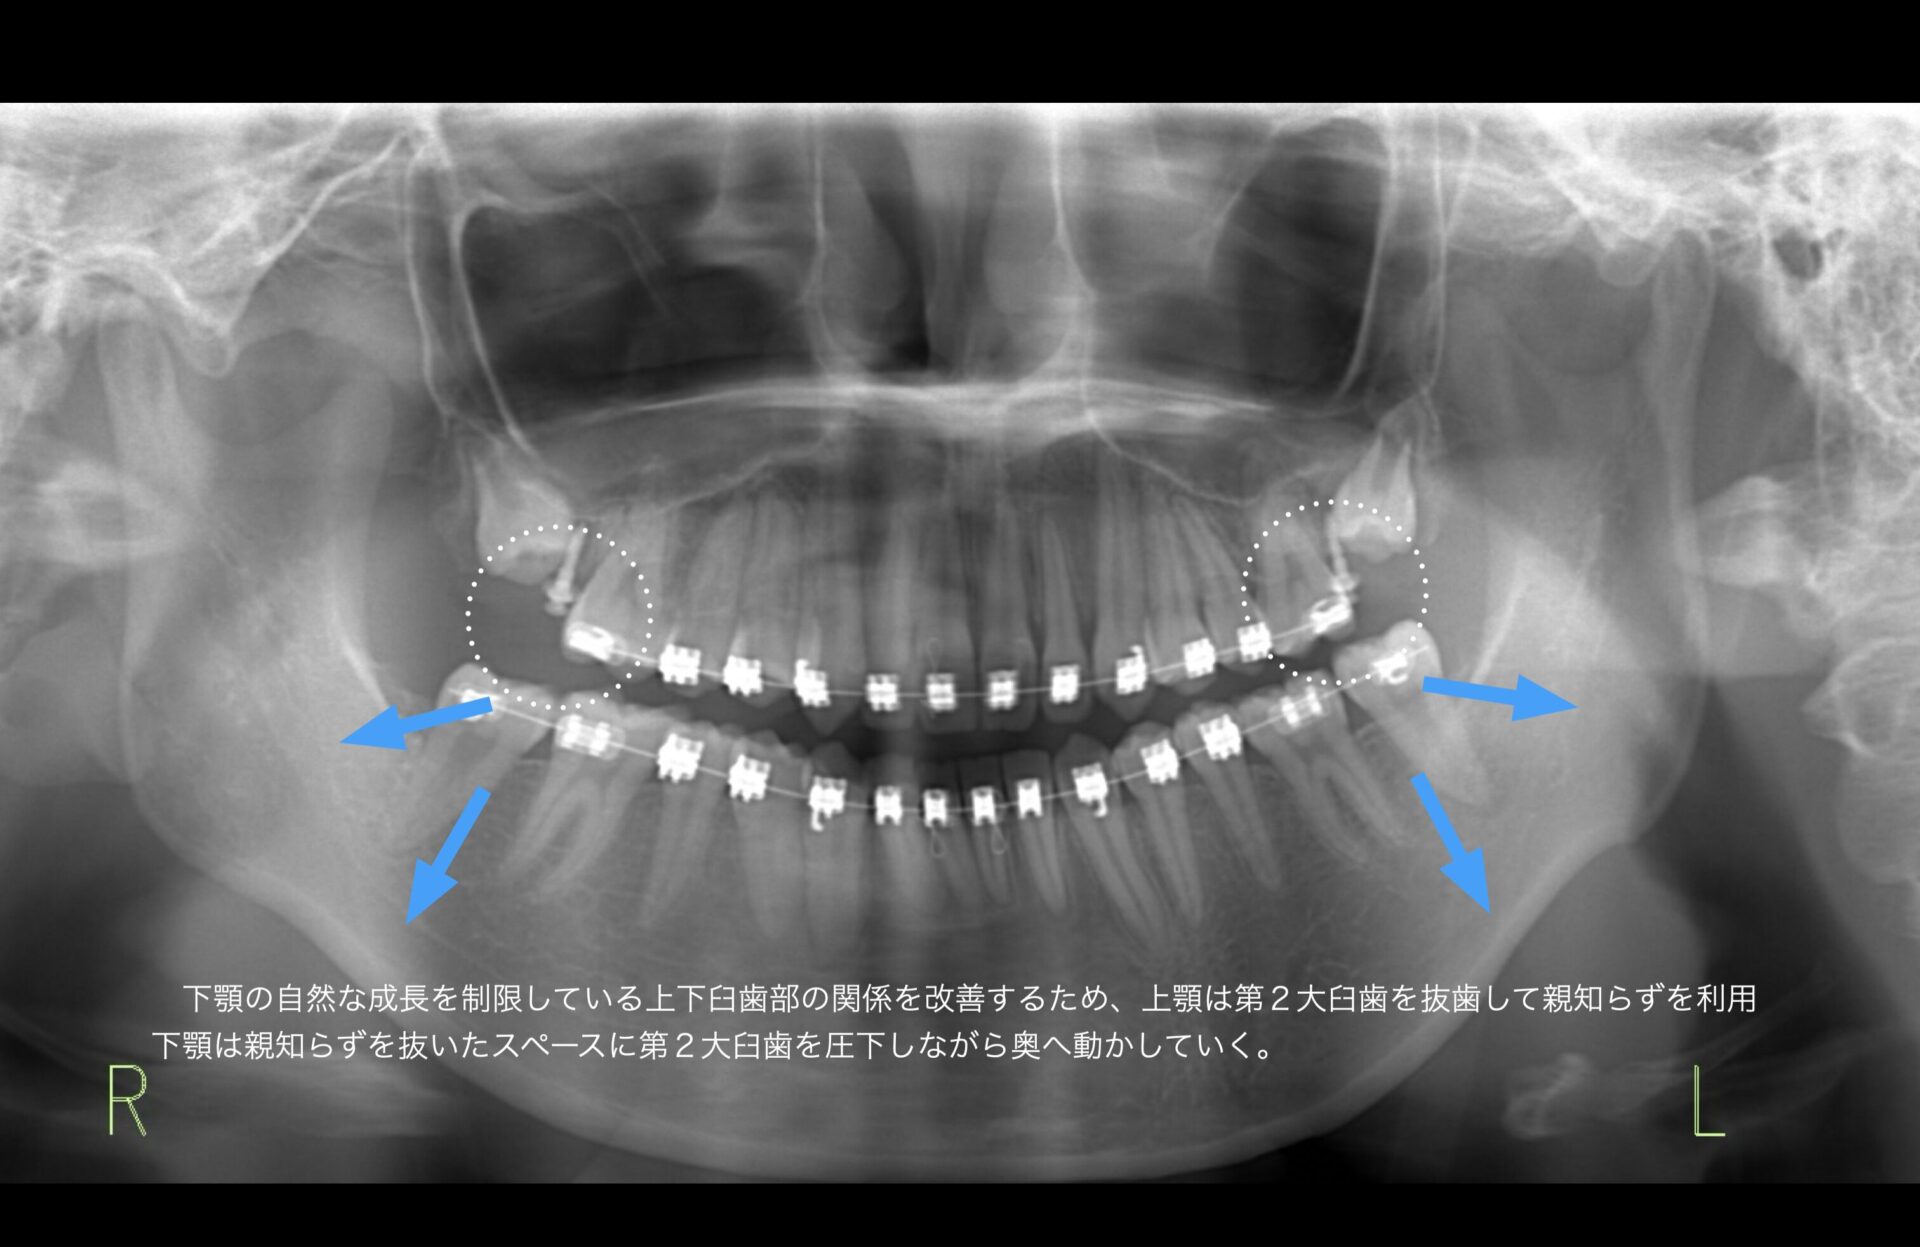

親知らずが上下左右存在する。下顎の前下方への成長を妨げている原因の一つと診断。下顎の親知らずを抜歯してから矯正をスタートする。

上顎第2大臼歯を抜歯して、その奥の親知らずを利用。下顎臼歯部は親知らずを抜いたスペースを利用して圧下。